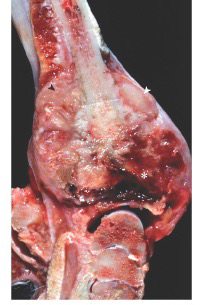

Osteomyelit og her kronisk purulent osteomyelit.

Hæmatogen spredning

De sætter sig her grundet karloops med fenestreret endothel, turbulens, nedsat flow, ringe fagocytosekapacitet, ingen kollateral blodforsyning og nogle bakterier har specifik adhæsion til brusk (Staph. Aureus).

Sequelae: Fisteldannelse (og arthritis), patologisk fraktur, sekvester, vækst-problemer og deformiteter.